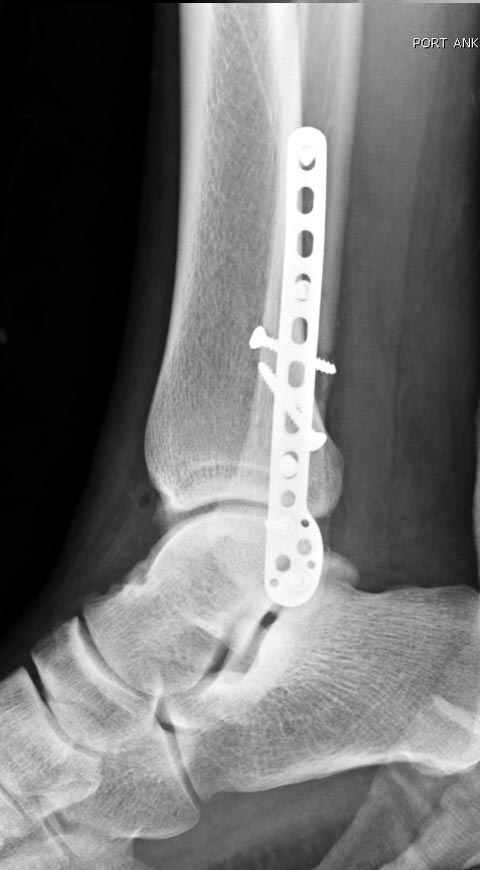

Тему неоднократно разбирали (см. архив), как всегда, недостаточны ренгенологические исследования - кроме прямого и боковых снимков, еще нужна косая ренгенограмма для определения ankle mortise, без мортиз снимка трудно определить высоту и ротацию малоберцовой. (снимки)

Показания для фиксации: укорочения и ротация малоберцовой, особенно обращают внимание на любой подвывих таранной кости: неустраненый подвывих впоследствии приводит к раннему артрозу. Задний край фиксирует тогда, когда перелом составляет около 25% суставной поверхности голеностопного сочленения и смещение более 2мм.

По снимку ваш случай относится к Weber В, фиксацию производят восстановлением длины малоберцовой кости, под ренгеном (ЭП)контролем, для этого я предпочел бы латеральный доступ, остеотомия по линии перелома, удлинение малоберцовой засчет скоса линии остеотомии, компрессия “lag technique”по линии остеотомии и фиксацию провести латеральной пластиной. Отдельный задний доступ, остеотомия по линии перелома, репозиция и фиксация заднего края вашим предпочтительным методом: 3.5мм шурупом с шайбой или пластиной Antiglide Butress

method. При восстановленном суставе, уменьшится медиальная щель, а при Weber В повреждается только передне-нижняя межберцовая связка синдесмоза, повреждение которой приводит к наружной ротации

малоберцовой, но после восстановления всех смещений, связка автоматический приближается к исходному и нет необходимости восстановления синдесмоза.